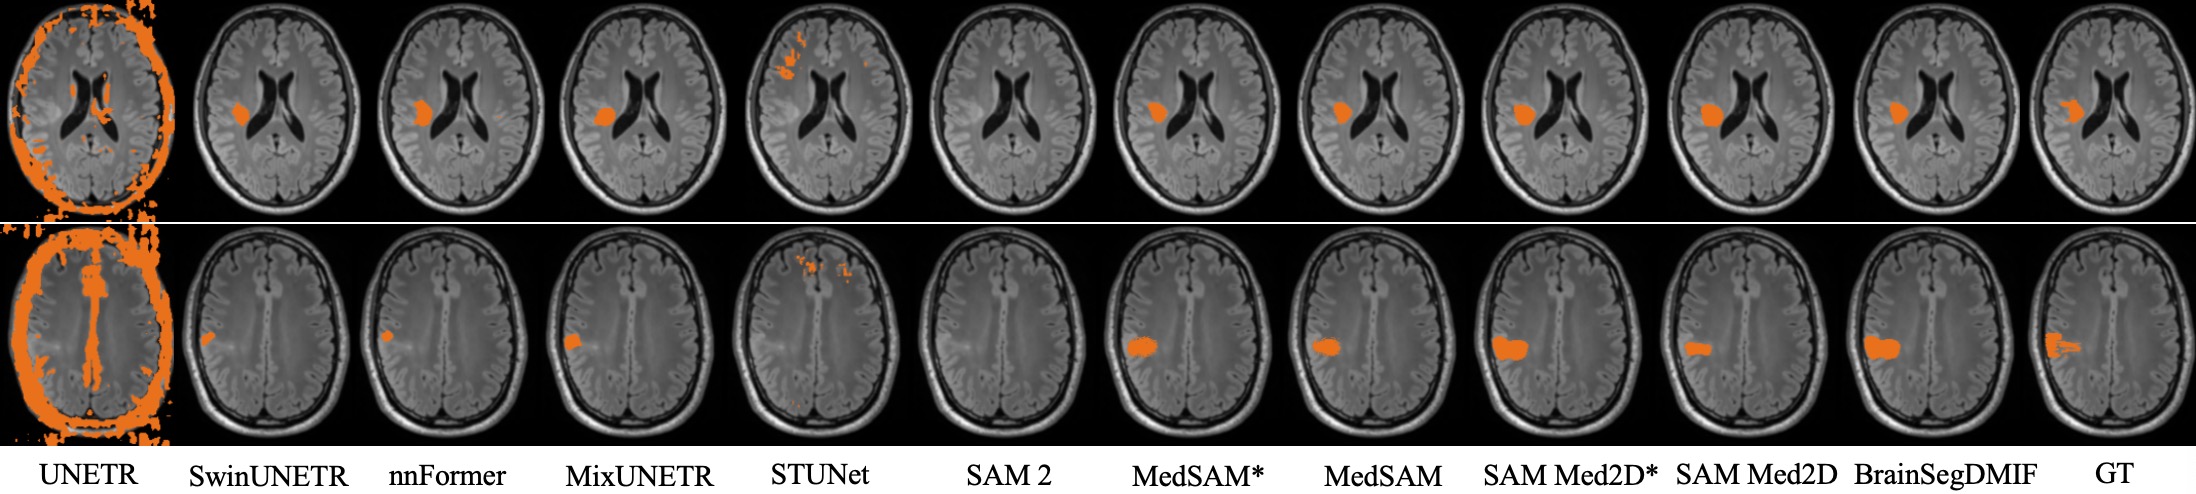

In this section, we conducted a quantitative comparison with several state-of-the-art methods, including UNETR(Hatamizadeh et al., 2022), SwinUNETR(Hatamizadeh et al., 2021), nnFormer(Zhou et al., 2023), MixUNETR(Shen et al., 2025), STUNet (Huang et al., 2023), SAM 2 (Ravi et al., 2024), MedSAM (Ma et al., 2024), and SAMMed2D(Cheng et al., 2023). To ensure a fair comparison, the comparison models used the FLAIR modality data, which showed the best segmentation results in Table 2, and were trained according to their default training protocols. The quantitative comparison results are presented in Table 1, where our method demonstrates superior performance across all datasets. Specifically, on the BraTS2021 dataset, our method achieved a Dice score of 79.64, an IoU of 68.55, a Precision of 81.88, and a Sensitivity of 78.24, outperforming the second-best method, SAM Med2D, by 7.25, 5.34, 11.09, and 2.56 points, respectively. On the FCD 2023 dataset, our model achieved a Dice score of 64.84, an IoU of 51.07, a Precision of 63.79, and a Sensitivity of 68.07, surpassing SAM Med2D by 7.36, 8.11, 7.48, and 9.16 points, respectively. Compared to MedSAM, which also leverages SAM, our method achieved a Dice score that was 7.96 higher, an IoU that was 6.59 higher, a Precision that was 7.53 higher, and a Sensitivity that was 10.36 higher on the BraTS2021 dataset. The superior segmentation performance of our method can be attributed to modal interaction during training, enabling the model to learn domain knowledge from multimodal data and capture data from different perspectives. Figure 4 shows the segmentation results of various methods on the BraTS21 dataset, illustrating that our method better identifies lesion regions. Figure 5 presents the segmentation results of each method on the FCD2023 dataset, where our method more effectively distinguishes between lesion and non-lesion regions.